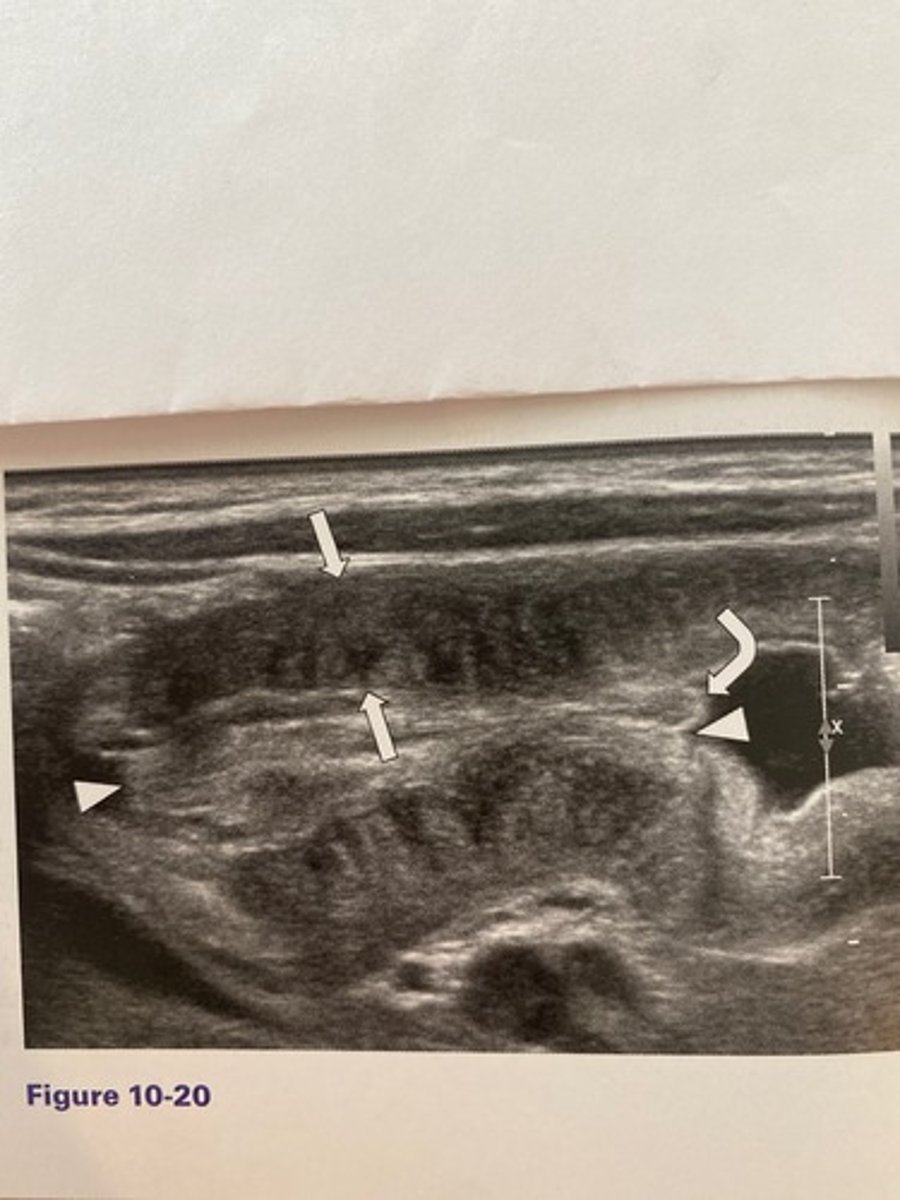

The measurement identified by the arrows in

Figure 10-20 should not exceed:

a. 2 mm.

b. 3 mm.

c. 3.5 mm.

d. 6 mm.

What is the most common age range at which the abnormality occurs in Figure 10-20?

a. 5 to 10 years of age

b. 1 to 4 weeks of age

c. 3 months to 3 years of age

d. 2 to 6 weeks of age

What is the sonographic sign noted in Figure

10-20?

a. Doughnut sign

b. Pyloric sign

c. Cervix sign

d. Cinnamon-bun sign

What would be the least likely clinical finding associated with Figure 10-20?

a. Weight gain

b. Olive sign

c. Projectile vomiting

d. Dehydration

What are the diagnostic criteria for pyloric stenosis?

a. 17 mm in thickness and 2 mm in length

b. 17 mm in thickness and 3 mm in length

c. 3 mm in thickness and 10 mm in length

d. 3 mm in thickness and 17 mm in length